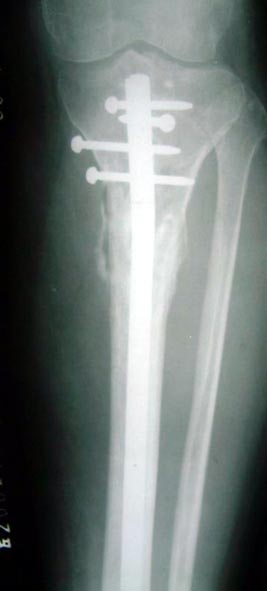

图1-2 将异体骨裁剪成12厘米长的骨板,将患者自体骨髓细胞经特殊处理后,

与松质骨和骨生长因子复合,形成成骨细胞和提供支撑力巧妙集合在一起的复合物,

使没有细胞的植骨材料变成了有细胞的活骨,新骨形成的效果得以大大加强。

图1-3 将异体骨--患者自体骨髓细胞---松质骨和骨生长因子复合物植入

图1-4 8个月后骨折愈合,12个月后去掉外固定架,可以负重行走,恢复工作。